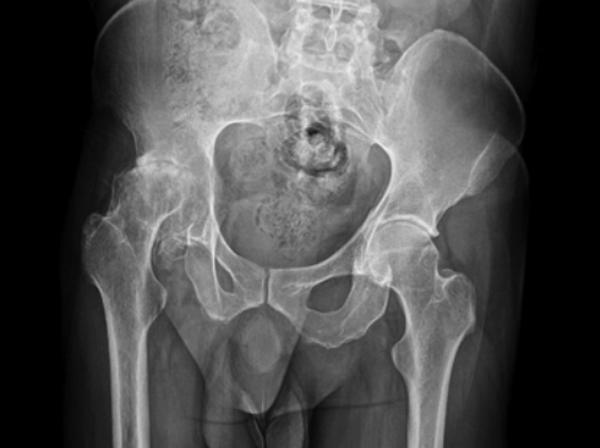

• Sarcoma de Ewing

Sarcoma de Ewing

Dr. James Ewing. Los sitios en los que este cáncer se desarrolla más comúnmente son la pelvis, la pared torácica (por ejemplo, las costillas o los omóplatos), y los huesos largos de las piernas o los brazos.